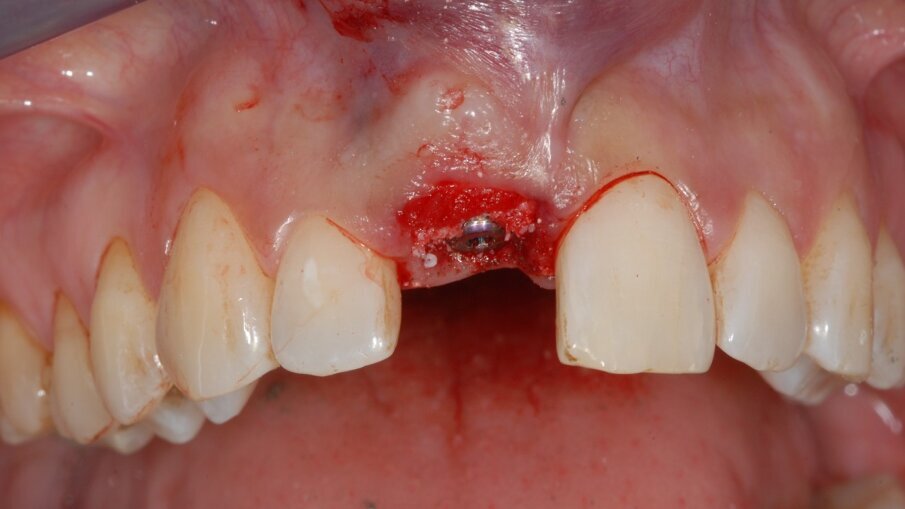

Infine, visto che la forma, lo spessore e la quota di gengiva cheratinizzata erano ideali, i tessuti sono stati elevati a tunnel attraverso la parabola senza nessuna incisione di rilascio ed è stata inserita una matrice dermica (Creos Mucogain, Nobel Biocare, Swiss) per migliorare e mantenere il tono dei tessuti stessi al posto di un più classico innesto di tessuto autologo connettivale (Fig. 3).

Fig. 3 - Appena inserito l’impianto il gap tra impianto e osso alveolare è stato zeppato con del biomateriale e tra i tessuti molli e il piatto osseo buccale è stata inserita una matrice dermica.